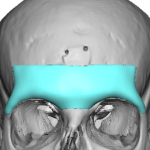

“Aesthetic temporal reduction” (often called temporal narrowing surgery) is a niche craniofacial procedure aimed at reducing the width of the head in the temple region (the area above and slightly behind the eyes). What it targets The temporal region (sides of the skull) Specifically: Temporal bone (outer skull) Temporalis muscle (a chewing muscle that can add bulk) How it’s done Read More…